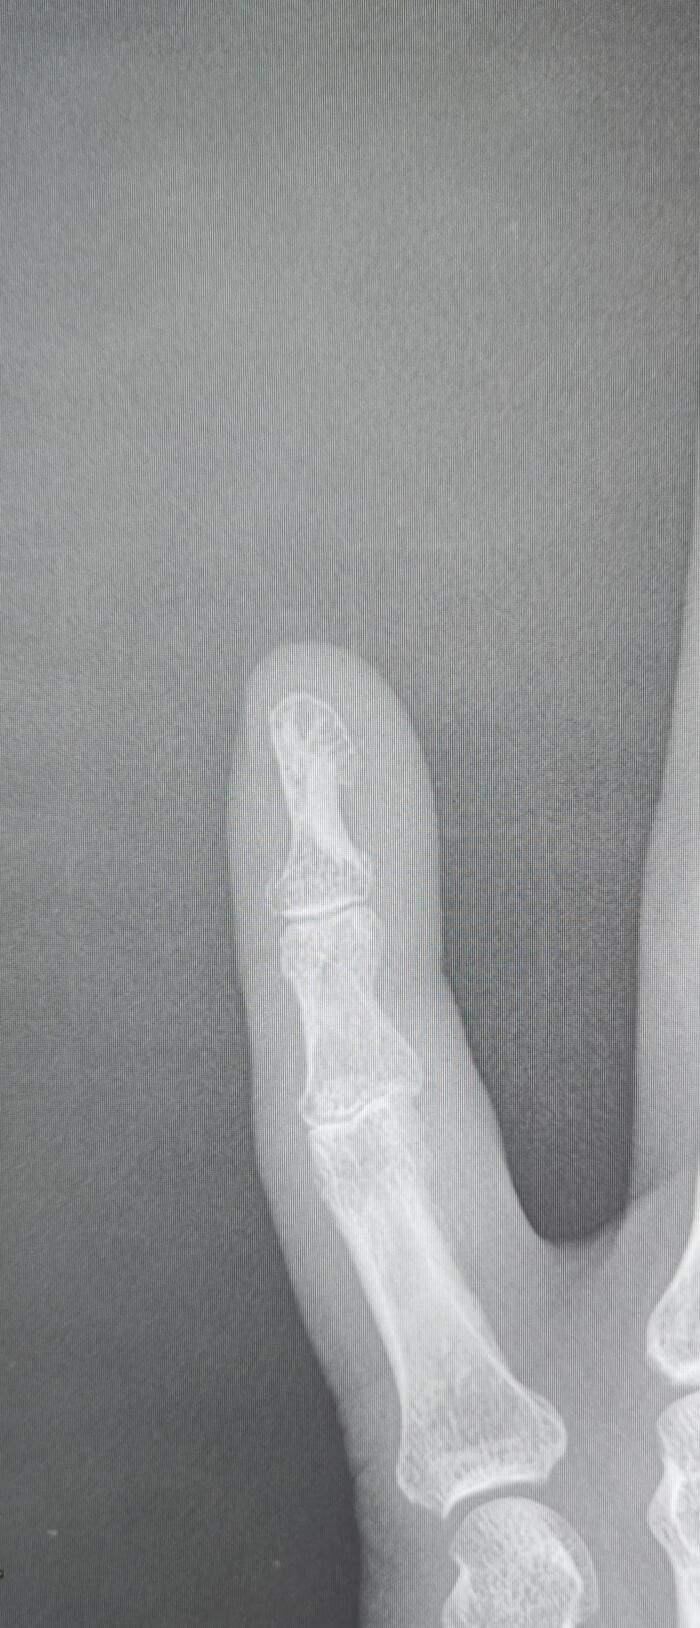

-Компактный костный островок(эностоз) дистальной фаланги пятого пальца правой кисти.

Основные рентгенологические признаки эностоза включают:

1. Очаговое затемнение:

• На рентгенограмме эностоз выглядит как четко очерченный очаг повышенной плотности (гиперденсивный) в костной ткани.

2. Форма и контуры:

• Образование обычно имеет округлую или овальную форму.

• Контуры четкие, ровные, иногда могут быть слегка лучистыми или неровными, но без признаков агрессивного роста.

3. Локализация:

• Эностоз может встречаться в любой кости, но чаще всего обнаруживается в губчатом веществе костей (например, в позвонках, тазовых костях, ребрах, длинных трубчатых костях).

4. Размер:

• Размеры эностоза обычно небольшие (от нескольких миллиметров до 1-2 см), но могут варьироваться.

5. Отсутствие деструкции окружающих тканей:

• Эностоз не вызывает разрушения окружающей костной ткани и не сопровождается периостальной реакцией.

6. Стабильность:

• При динамическом наблюдении эностоз обычно не изменяется в размерах или растет очень медленно.

7. Связь с костными трабекулами:

• Эностоз часто сливается с окружающими костными трабекулами, что создает характерный "лучистый" вид.

8. Отсутствие мягкотканного компонента:

• Эностоз не сопровождается образованием мягкотканного компонента или внекостного распространения.